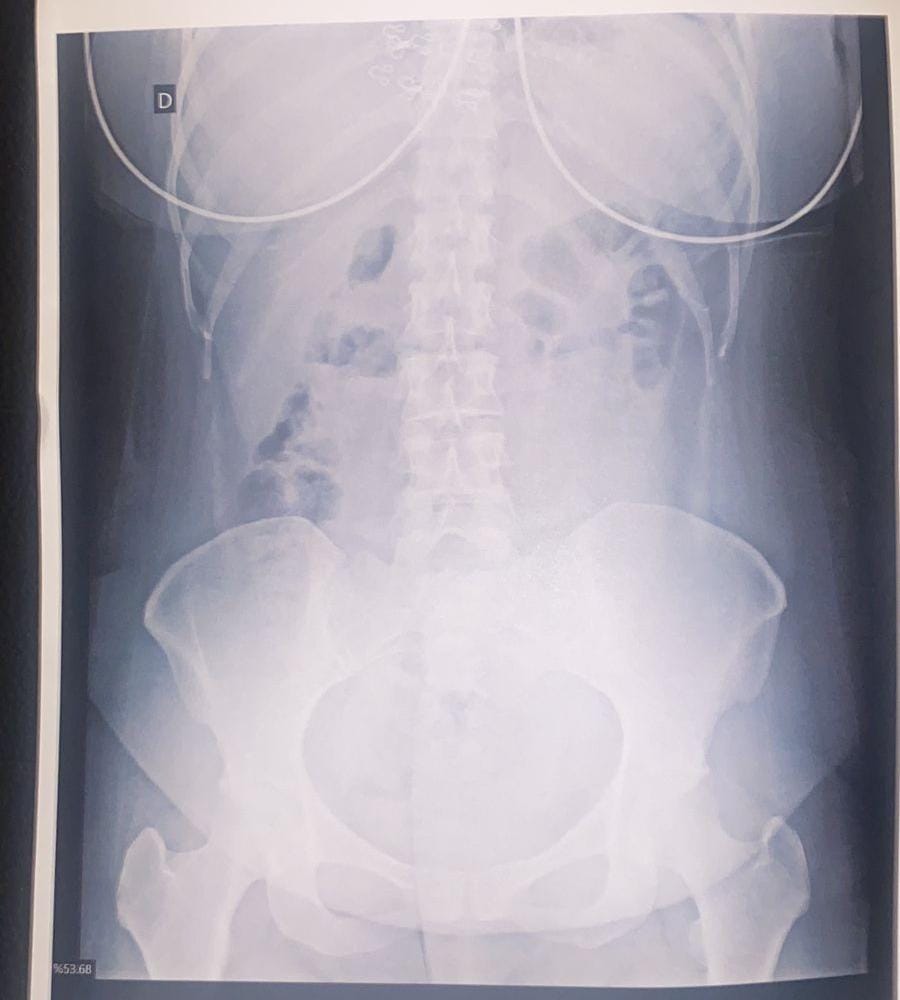

O suspeito, também, declarou que havia ingerido algumas das cápsulas e foi levado à Santa Casa de Corumbá. Ele foi submetido a um exame de Raio-X, que constatou aproximadamente 30 cápsulas ingeridas. No total, foram identificadas 95 cápsulas de droga sob porte do casal.